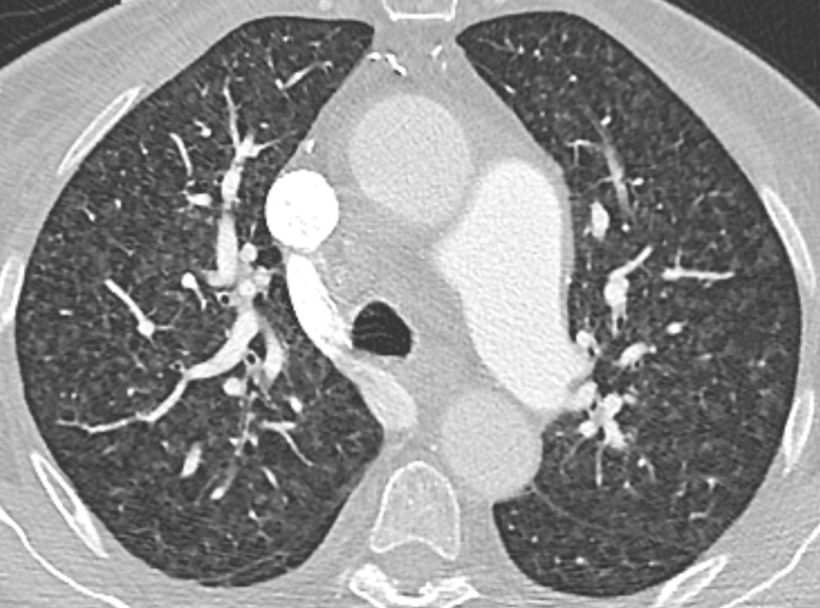

Airway disease - Bronchiectasis

Irreversible localized or diffuse bronchial dilatation, usually resulting from chronic infection, proximal airway obstruction, or congenital bronchial abnormality.